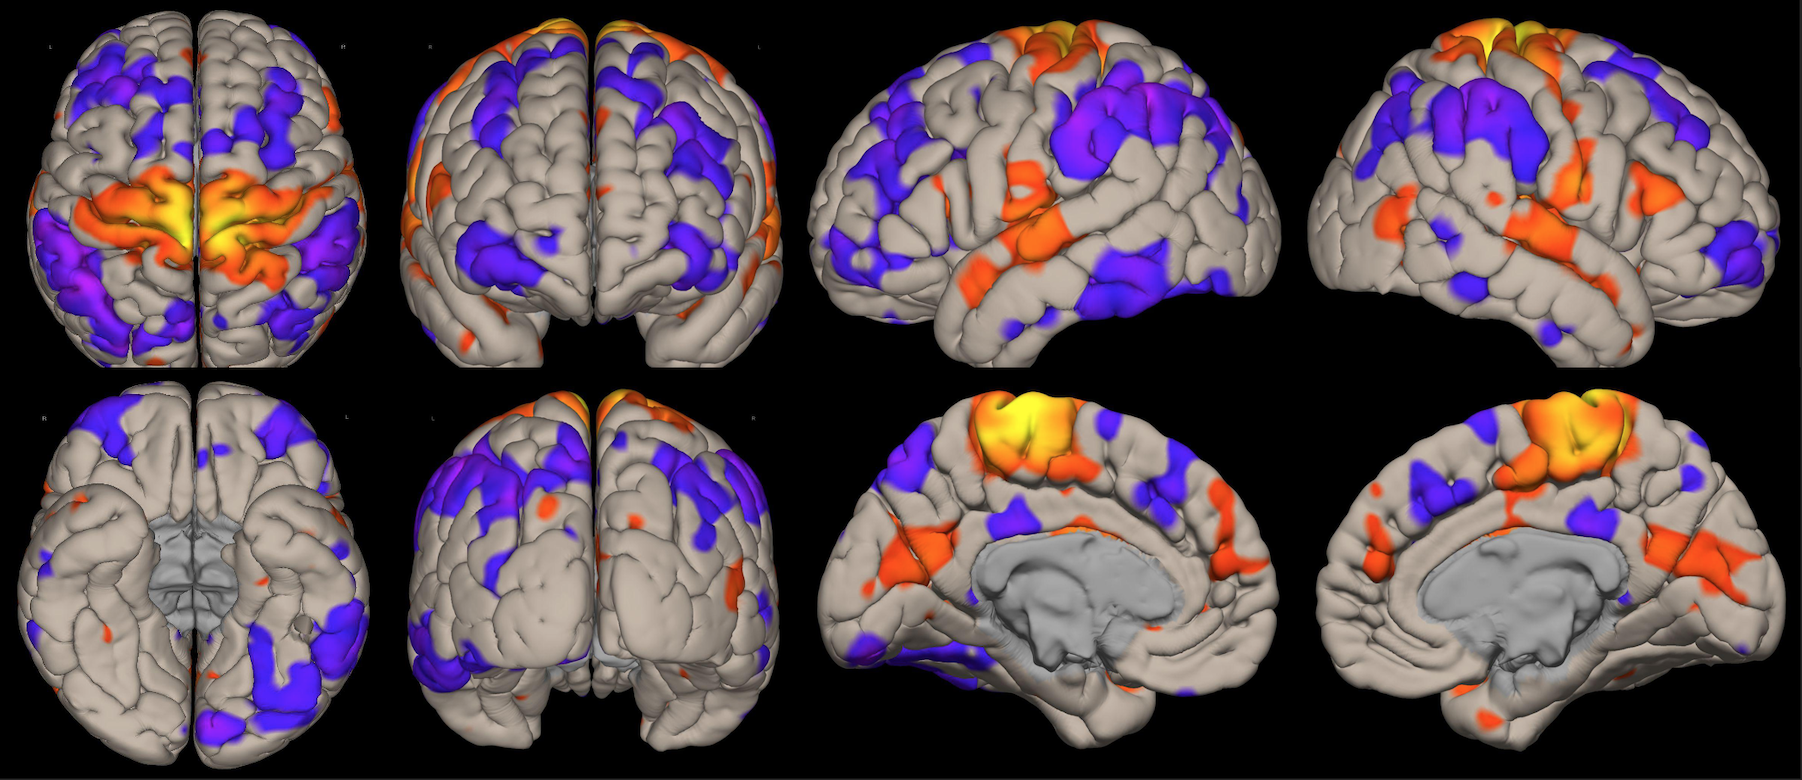

DISTINTAS CONEXIONES CEREBRALES EN ESTADO DE REPOSO

A pesar de la ausencia actividad física, resulta imposible indicar que no se esté realizando ningún tipo de actividad mental, como recuerdos o el uso de la imaginación. La consecuencia de esto se ve reflejada en los cambios de la actividad neuronal.16 A través de este método de vóxel semilla se ha logrado identificar distintas redes de conectividad funcional descritos a continuación:

Red de Atención Dorsal:

Constituida por la corteza cingular anterior, ambas ínsulas y el área motora suplementaria, la cual juega un rol importante en la regulación de los cambios dinámicos en las otras redes, por lo que su disfunción afecta directamente en el correcto funcionamiento de las otras redes. Otra característica conocida, es la necesidad de operatividad de esta área para la realización de rápidos cambios de comportamiento. Evidentemente, el inicio del control de los procesos de cognición se ve determinado por el correcto funcionamiento de esta red sobresaliente.

Esta red la constituyen los ganglios basales, sustancia negra, núcleo subtalámico, núcleo estriado y el globo pálido. Estas estructuras localizadas en la región basal del cerebro están involucradas en muchas funciones como la modulación de las áreas motoras, cognición y emociones. Consecuentemente, forman parte del aprendizaje de comportamientos complejos y difíciles, debido a la gran coordinación durante la realización de movimiento involucrado estas actividades.

Red Visual:

Se ha reportado la activación sincrónica en los surcos calcáreos, regiones extraestriadas, área inferior de la precuña y el núcleo geniculado lateral del tálamo, el cual se conecta funcionalmente con la corteza visual primaria en el lóbulo occipital. Estos a su vez se organizan en áreas visual medial (región extraestriada, división inferior de la precuña y núcleo geniculado lateral) y lateral (unión occipito temporal abarcando el polo occipital y la región parietal superior).

Red Visuo-Espacial:

Asociada a la red visual, compuesto por la corteza parietal posterior de la unión occipito parietal, región media de la precuña, corteza cingular posterior y el polo frontal, por lo que la afección de estas regiones puede afectar la atención espacial del individuo. Por lo que se infiere que la corteza parietal posterior está involucrada en orientarse hacia señales visuoespaciales sobresalientes.

Red “Modo por Defecto”:

Involucra la corteza cingular posterior, corteza prefrontal medial y la corteza parietal lateral. La actividad de esta red se ve incrementada en el caso de que la persona en estudio esté en una condición de reposo, observándose una especie de desactivación al realizar algunas tareas. Esta red tiene participación también en algunos aspectos sociales como la introspección, divagación, procesamiento emocional, entre otros.

Red Precuña:

Área asociada con la red “modo por defecto”, caracterizada con zonas de alta tasa metabólica comparado con otras redes durante el estado de reposo. Se ha reportado la importancia de esta área, interviniendo en funciones de comportamiento; así como en la manipulación de imágenes mentales y atención guiada internamente, derivada del estudio de imágenes visuoespaciales.

Red del Lenguaje:

Implica las regiones prefrontales, temporo-parietal y subcortical, además de las ya conocidas áreas de Broca y Wernicke. El habla, el entendimiento, lectura, interpretación, mímicas; son algunas de las funciones más importantes de esta red. Adicionalmente, el área de Broca es asiento de las neuronas espejo, las cuales intervienen en el entendimiento e imitación de actividades motoras.

Red Ejecutiva y Red del Control Ejecutivo

La red ejecutiva es la red que se activa al realizar exámenes como la resonancia magnética funcional basada en tareas, y se encuentra compuesta por la corteza prefrontal dorsolateral y corteza parietal posterior. Mientras que la red del control ejecutivo comprende el giro frontal medio, giro frontal superior, la corteza anterior del cíngulo, giro paracingular, corteza prefrontal ventrolateral y regiones subcorticales del tálamo. Esta red se activa durante las tareas que requieren el uso de la cognición y memoria procedimental. Principalmente suele verse en caso de actividades dirigidas y durante la realización de actividades intelectuales.

Red Sensorio-Motora:

Primera red en ser estudiada usando el método de vóxel semilla, la cual muestra la alta correlación entre las regiones motoras del hemisferio izquierdo y derecho. En esta corteza sensorio-motora, las áreas de Broddman, localizadas en la región posterior al surco central, el giro precentral y la corteza auditiva primaria, forman parte de esta red, en asociación con los núcleos ventral laterales y ventral posterior del tálamo. La activación de esta red interviene directamente en la percepción de estímulos sensorio-motores, auditivos y en el planeamiento y ejecución para el movimiento de los músculos.

Red Auditiva:

Red asociada a la red sensorio motora, comprendido por la corteza auditiva primaria bilateral, giro temporal transverso, planum polare y temporale, giro temporal supero-lateral y corteza insular posterior. Las cortezas auditivas se encuentran bien definidas para como confiables para el giro temporal transverso de cada lado respectivamente.